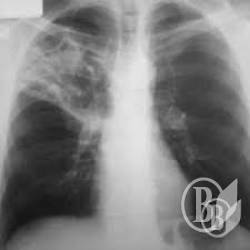

Хворих на туберкульоз залишили без ліків

Нещодавно між одним із пацієнтів Чернігівського протитуберкульозного диспансеру та керівництвом лікарні склалась конфліктна ситуація.

ЧИТАЙТЕ ТАКОЖ: Вразливі категорії населення перевірили на туберкульоз